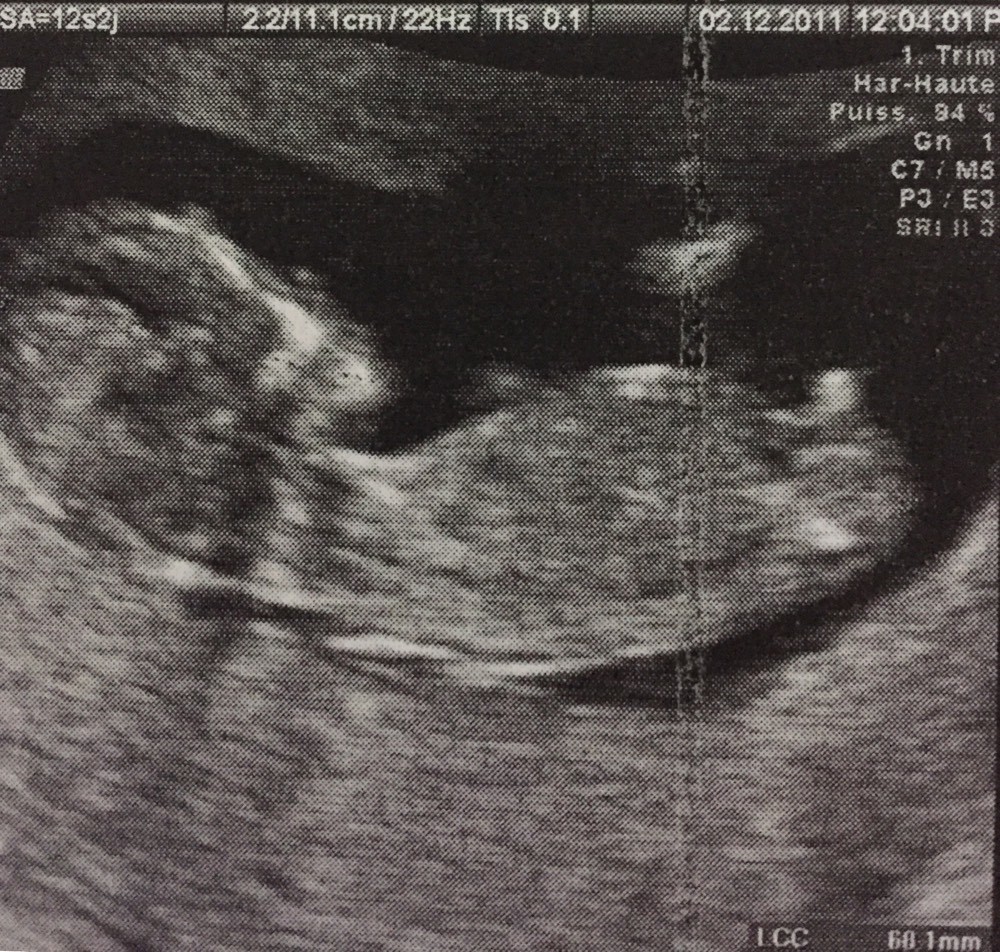

Echo 12 SA 3 jours le 27/07 bébé mesure 63cm et son coeur bat à 153p/m 80% de chances que tu sois une petite princesse On t'aime !30 août 12 To be or not to be PMA Catégories Grossesse Étiquettes Echographie 12 saLa clarté nucale voilà un élément morphologique dont on ignore généralement totalement l'existence tant qu'on a pas été enceinteQu'estce donc ?

A voir également Sexe bébé 12 SA Gouter bebe 12 mois Guide Taille bebe 12 sa Guide Miel bebe 12 mois Guide Journée type bébé 12 mois Guide Bebe 12 kg quel age Guide Votre réponseRendezvous avec nos 2 petits bébés d'amour11ème semaine de grossèsseOn la mesure lors du premier trimestre (jusqu'à 14 SA) Elle est de 55 mm en moyenne à 12 SA PC Périmètre Céphalique ou Crânien Il s'agit du tour de tête de votre bébé A la première échographie (12 SA) 68 mm en moyenne A la seconde échographie (22 SA) 199 mm en moyenne A la troisième échographie (32 SA) 297 mm en moyenne

Dernier message posté le à 10h54 Mélodie Nierengarten à 10h43 Alerter Copier le lien Le lien a été copié dans votre pressepapier Bonjour, Voici mon post parmi tant d'autres pour essayer de deviner le sexe de mon bébéLe soir de la première échographie OFFICIELLE celle des 12 semaines d'aménorrhée Nous sommes allés dans un cabinet d'échographie recommandé par madame gynécoSelon les mesures nous étions hier entre 12 sa 3 pour la longueur fémorale (qui est de 803 mm) à 12 sa 6 pour le périmètre crânien (qui est de 229 8mm), et avec 165 bpm pour la fréquence cardiaque !